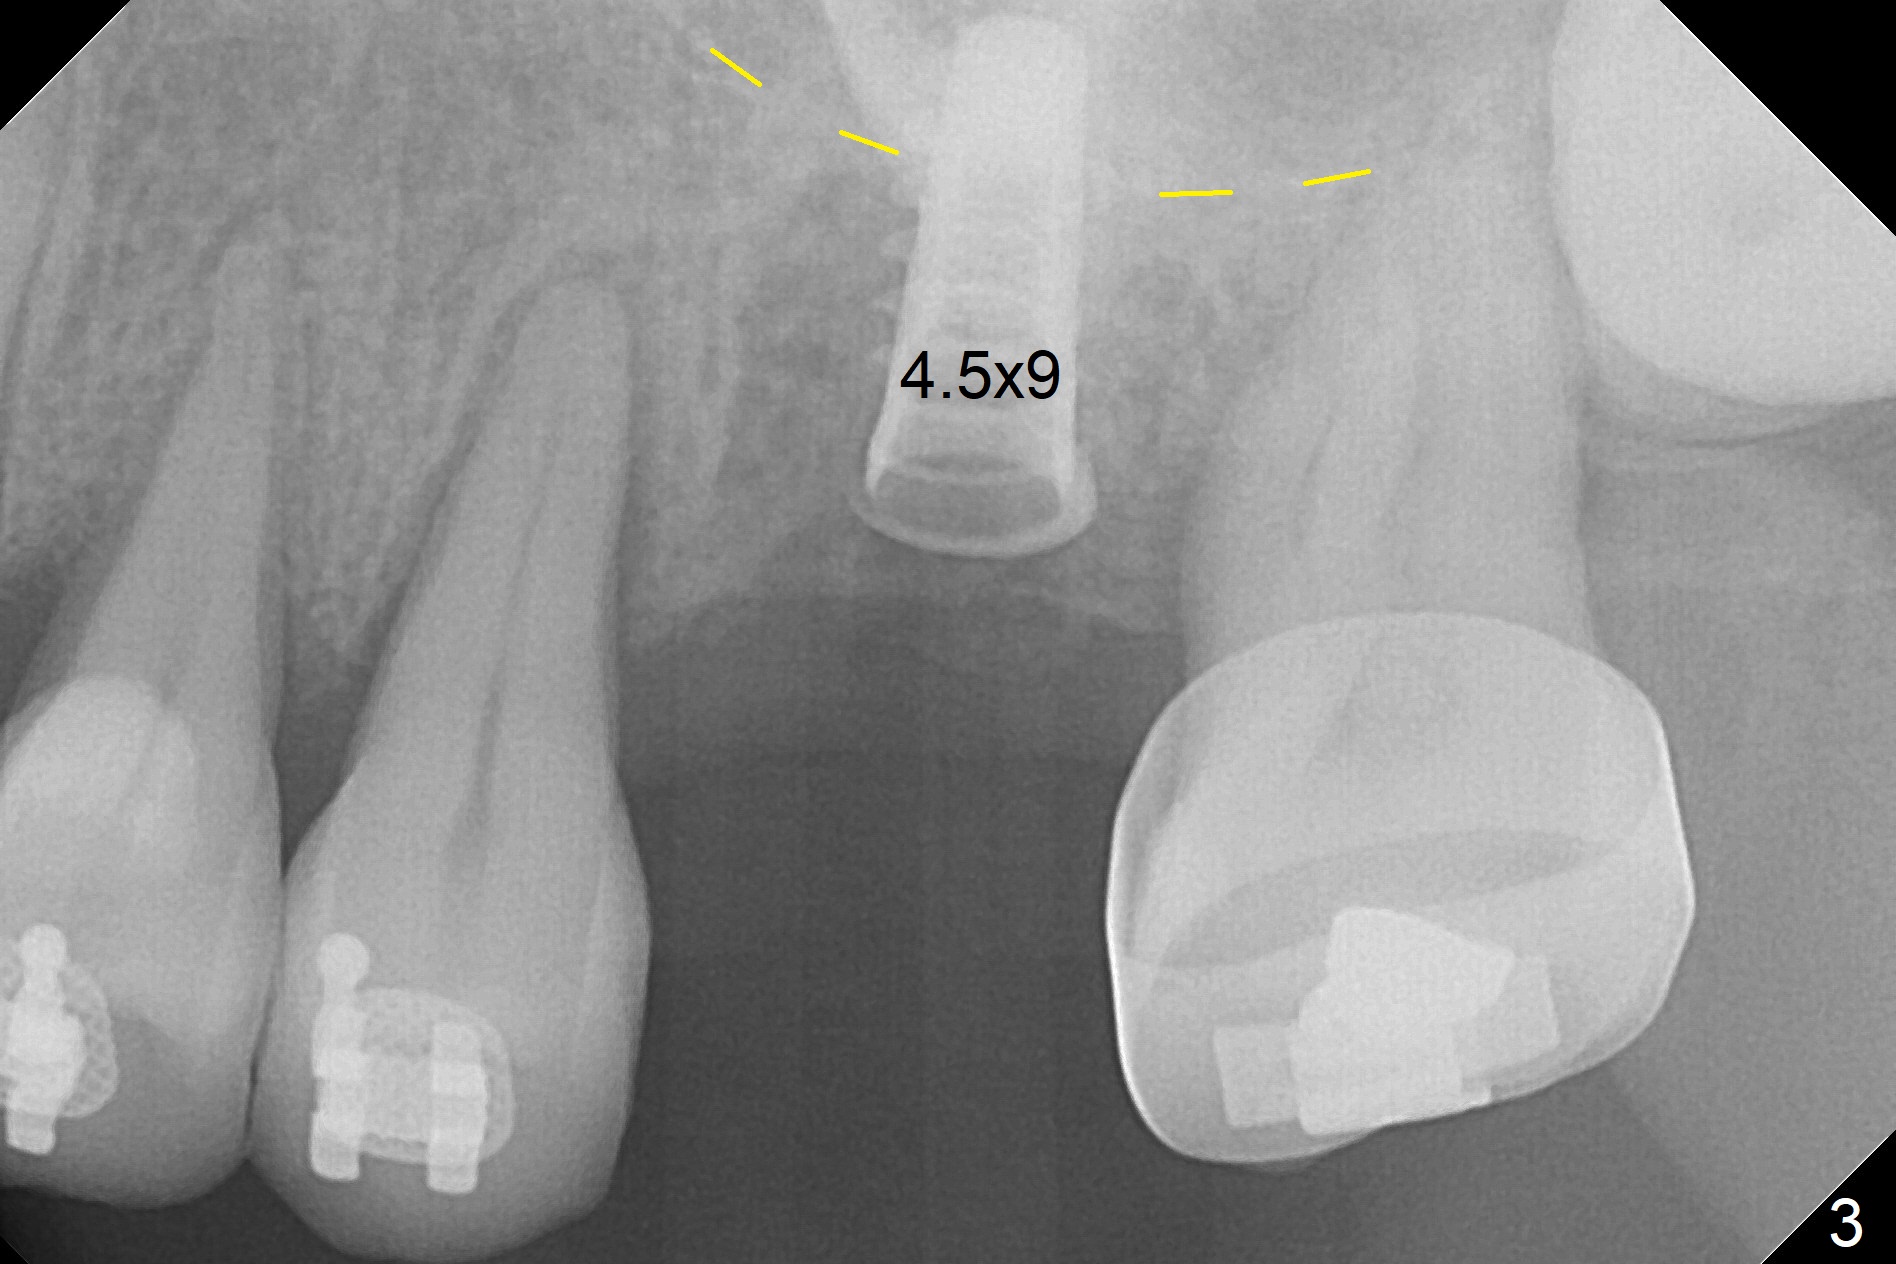

Preop exam shows the narrow ridge at #14. Magic split is used for access and initiation of osteotomy and bone expansion, followed by 3 mm Magic Expander for 11 mm (ME, Fig.1 (yellow line: sinus floor)). In fact the bone is soft. After use of 3.8 mm ME and Lindamann bur (to move the osteotomy distobuccally), a 4x11 mm dummy implant is placed with 20 Ncm (Fig.2). Following use of Lindamann bur for the same purpose as mentioned above, a 4.5x9 mm IBS implant is placed 3 mm subgingival with <30 Ncm (Fig.3,4). Bone graft is placed for sinus lift prior to implantation. A 5x3 mm healing abutment is placed. Bone loss is minimal 3.5 months postop (Fig.5) and striking 8 months postop (after crown cementation, Fig.6-8). The bone loss persists in spite of crown and abutment removal (Fig.9,10). Bone graft or implant redo is planned.